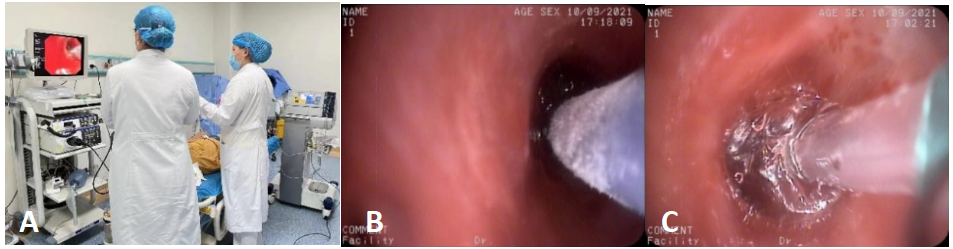

完善各项检查,排除相关禁忌症,分三步对患者进行了高频电切+冷冻治疗+球囊扩张的支气管镜下介入治疗。

第一步:高频电刀切开,快速畅通气道!

第二步:冷冻治疗,减轻瘢痕增生!

第三步:球囊扩张,使管腔持续扩张,避免再狭窄!

图3 第1次治疗(高频电切+冷冻治疗+球囊扩张2021/9/10)

A. 高频电切 B.冷冻治疗 C.球囊扩张

图6 支气管镜下介入治疗

A.高频电切 B.冷冻治疗 C.球囊扩张